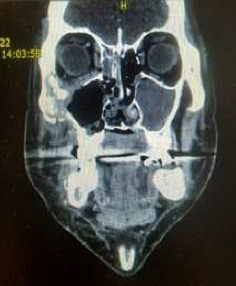

简介:毛霉病是一种罕见但严重的感染引起的真菌称为毛霉菌。它是一种危及生命的、高度侵袭性的血管侵入性感染,主要影响免疫功能低下的人群。方法和结果:2021年至2023年初,在塞尔维亚贝尔格莱德大学口腔医学院颌面外科诊所(“诊所”),医疗小组(“小组”)治疗了5名患有鼻-眶-脑型毛霉菌病的患者。在发现毛霉病之前,所有5名患者最近都已从COVID-19感染中康复。他们都在新冠肺炎专科医院度过了相当长的时间(平均住院1个月)。该小组根据2019冠状病毒病大流行时的毛霉病筛查诊断和管理指南(2019冠状病毒病患者指南/印度医学研究委员会,2021年5月出版,经世卫组织批准)对这些患者进行了治疗。治疗包括几个阶段,其中小组负责并开展早期诊断和手术干预阶段,而其他诊所的同事则协助进行毛霉病的其他治疗/管理阶段。结论:本文的目的是提出5例诊断为毛霉病的患者,特别关注两例因其病情接受手术干预作为抗真菌治疗的一部分的患者。

Introduction: Mucormycosis is a rare but serious infection caused by fungi called mucormycetes. It is life-threatening, highly aggressive angioinvasive infection, which mainly affects immunocompromised people. Methods and Results: During 2021-early 2023, at the Clinic for Maxillofacial Surgery, Faculty of Dental Medicine, University of Belgrade, Serbia (the "Clinic"), medical team (the "Team") treated five patients, with a rhino-orbital-cerebral form of mucormycosis. All five patients had recently recovered from COVID-19 infection prior to detection of mucormycosis. All of them spent a considerable amount of time (on average 1 month of hospitalization) at COVID-19 specialized hospitals. The Team treated these patients following the guidelines for screening diagnosis and management of mucormycosis at the time of the COVID-19 pandemic (COVID-19 patient guidelines/Indian Council of Medical Research, published in May 2021 approved by WHO). Treatment included several phases, out of which the Team was responsible for and carried out early diagnosis and surgical intervention phase, while colleagues from other clinics assisted in other phases of treatment/management of mucormycosis. Conclusion: The goal of this paper is to present five patients diagnosed with mucormycosis, with a special focus on two patients who, due to their condition, received surgical intervention as part of their antifungal treatment.